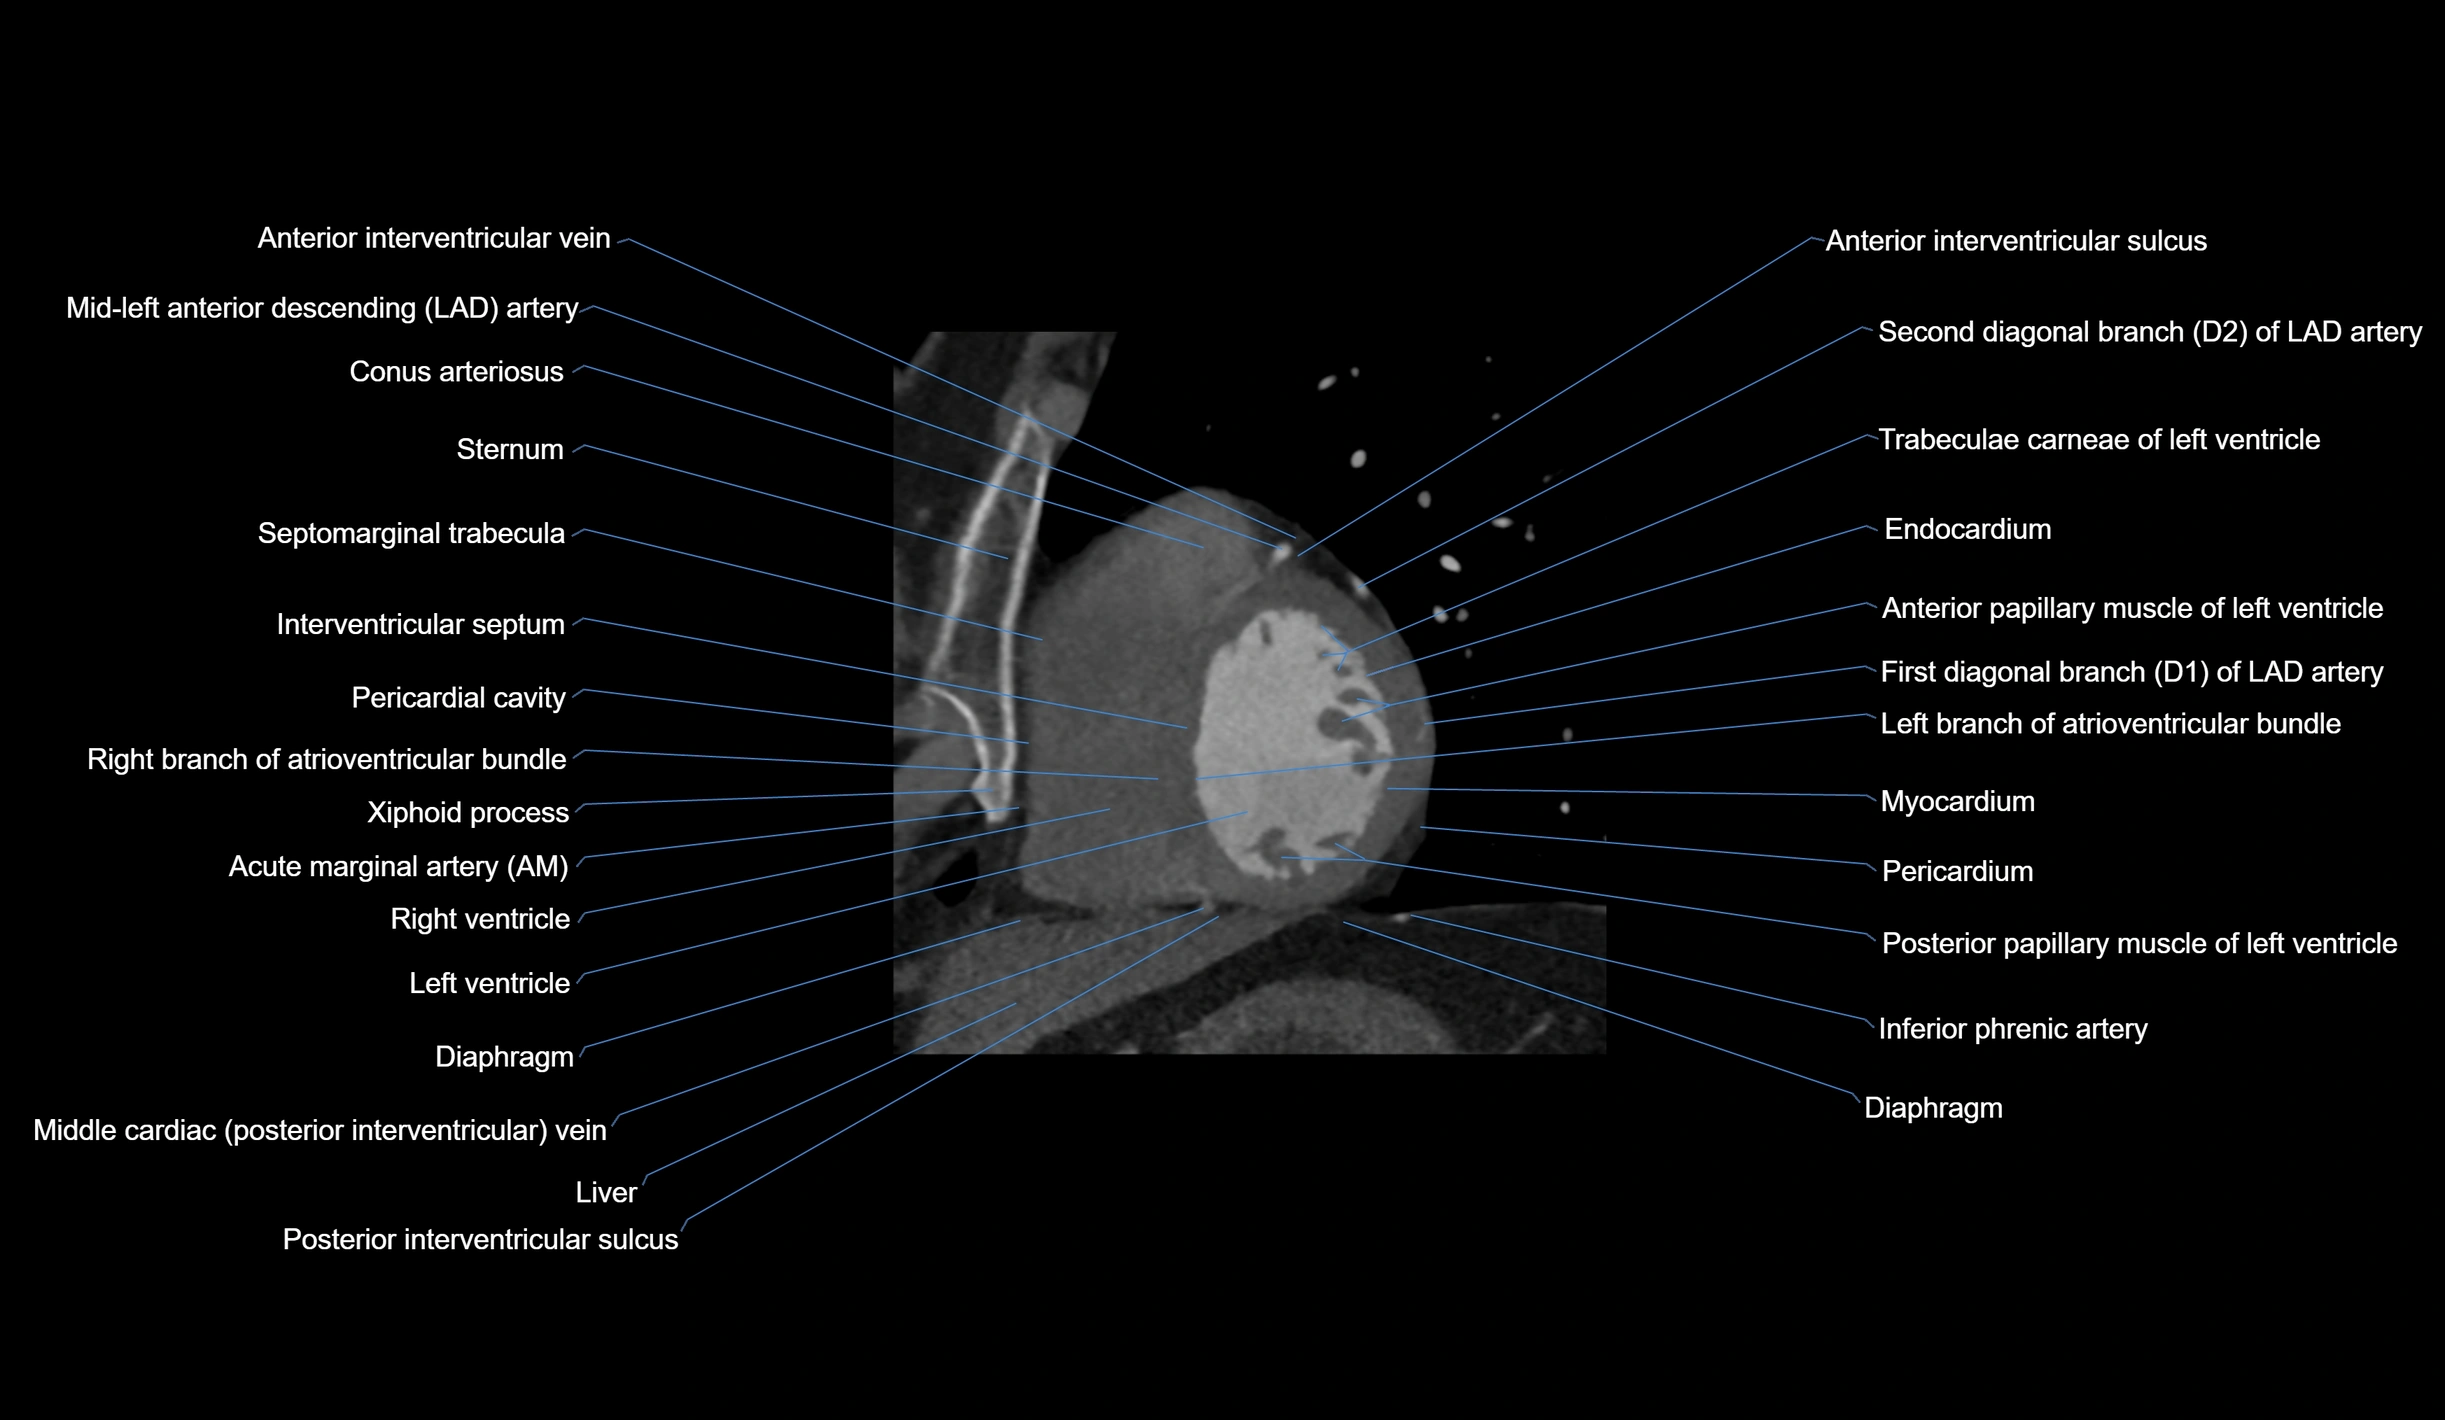

CT Appearance

Non-contrast CT (Calcium Scoring):

-

AM artery visualized for coronary calcium scoring

Calcified plaques appear as hyperdense foci; scored with Agatston method

CT Coronary Angiography (CCTA):

Best non-invasive modality for acute marginal artery visualization

Shows origin, course along the acute margin, and right ventricular branches

Detects stenosis, occlusion, calcified and non-calcified plaques, aneurysm, or anomalous course

Multiplanar reformats and 3D reconstructions help in pre-PCI and surgical planning

Critical for assessing right ventricular infarction risk in RCA disease

MRI image

CT images